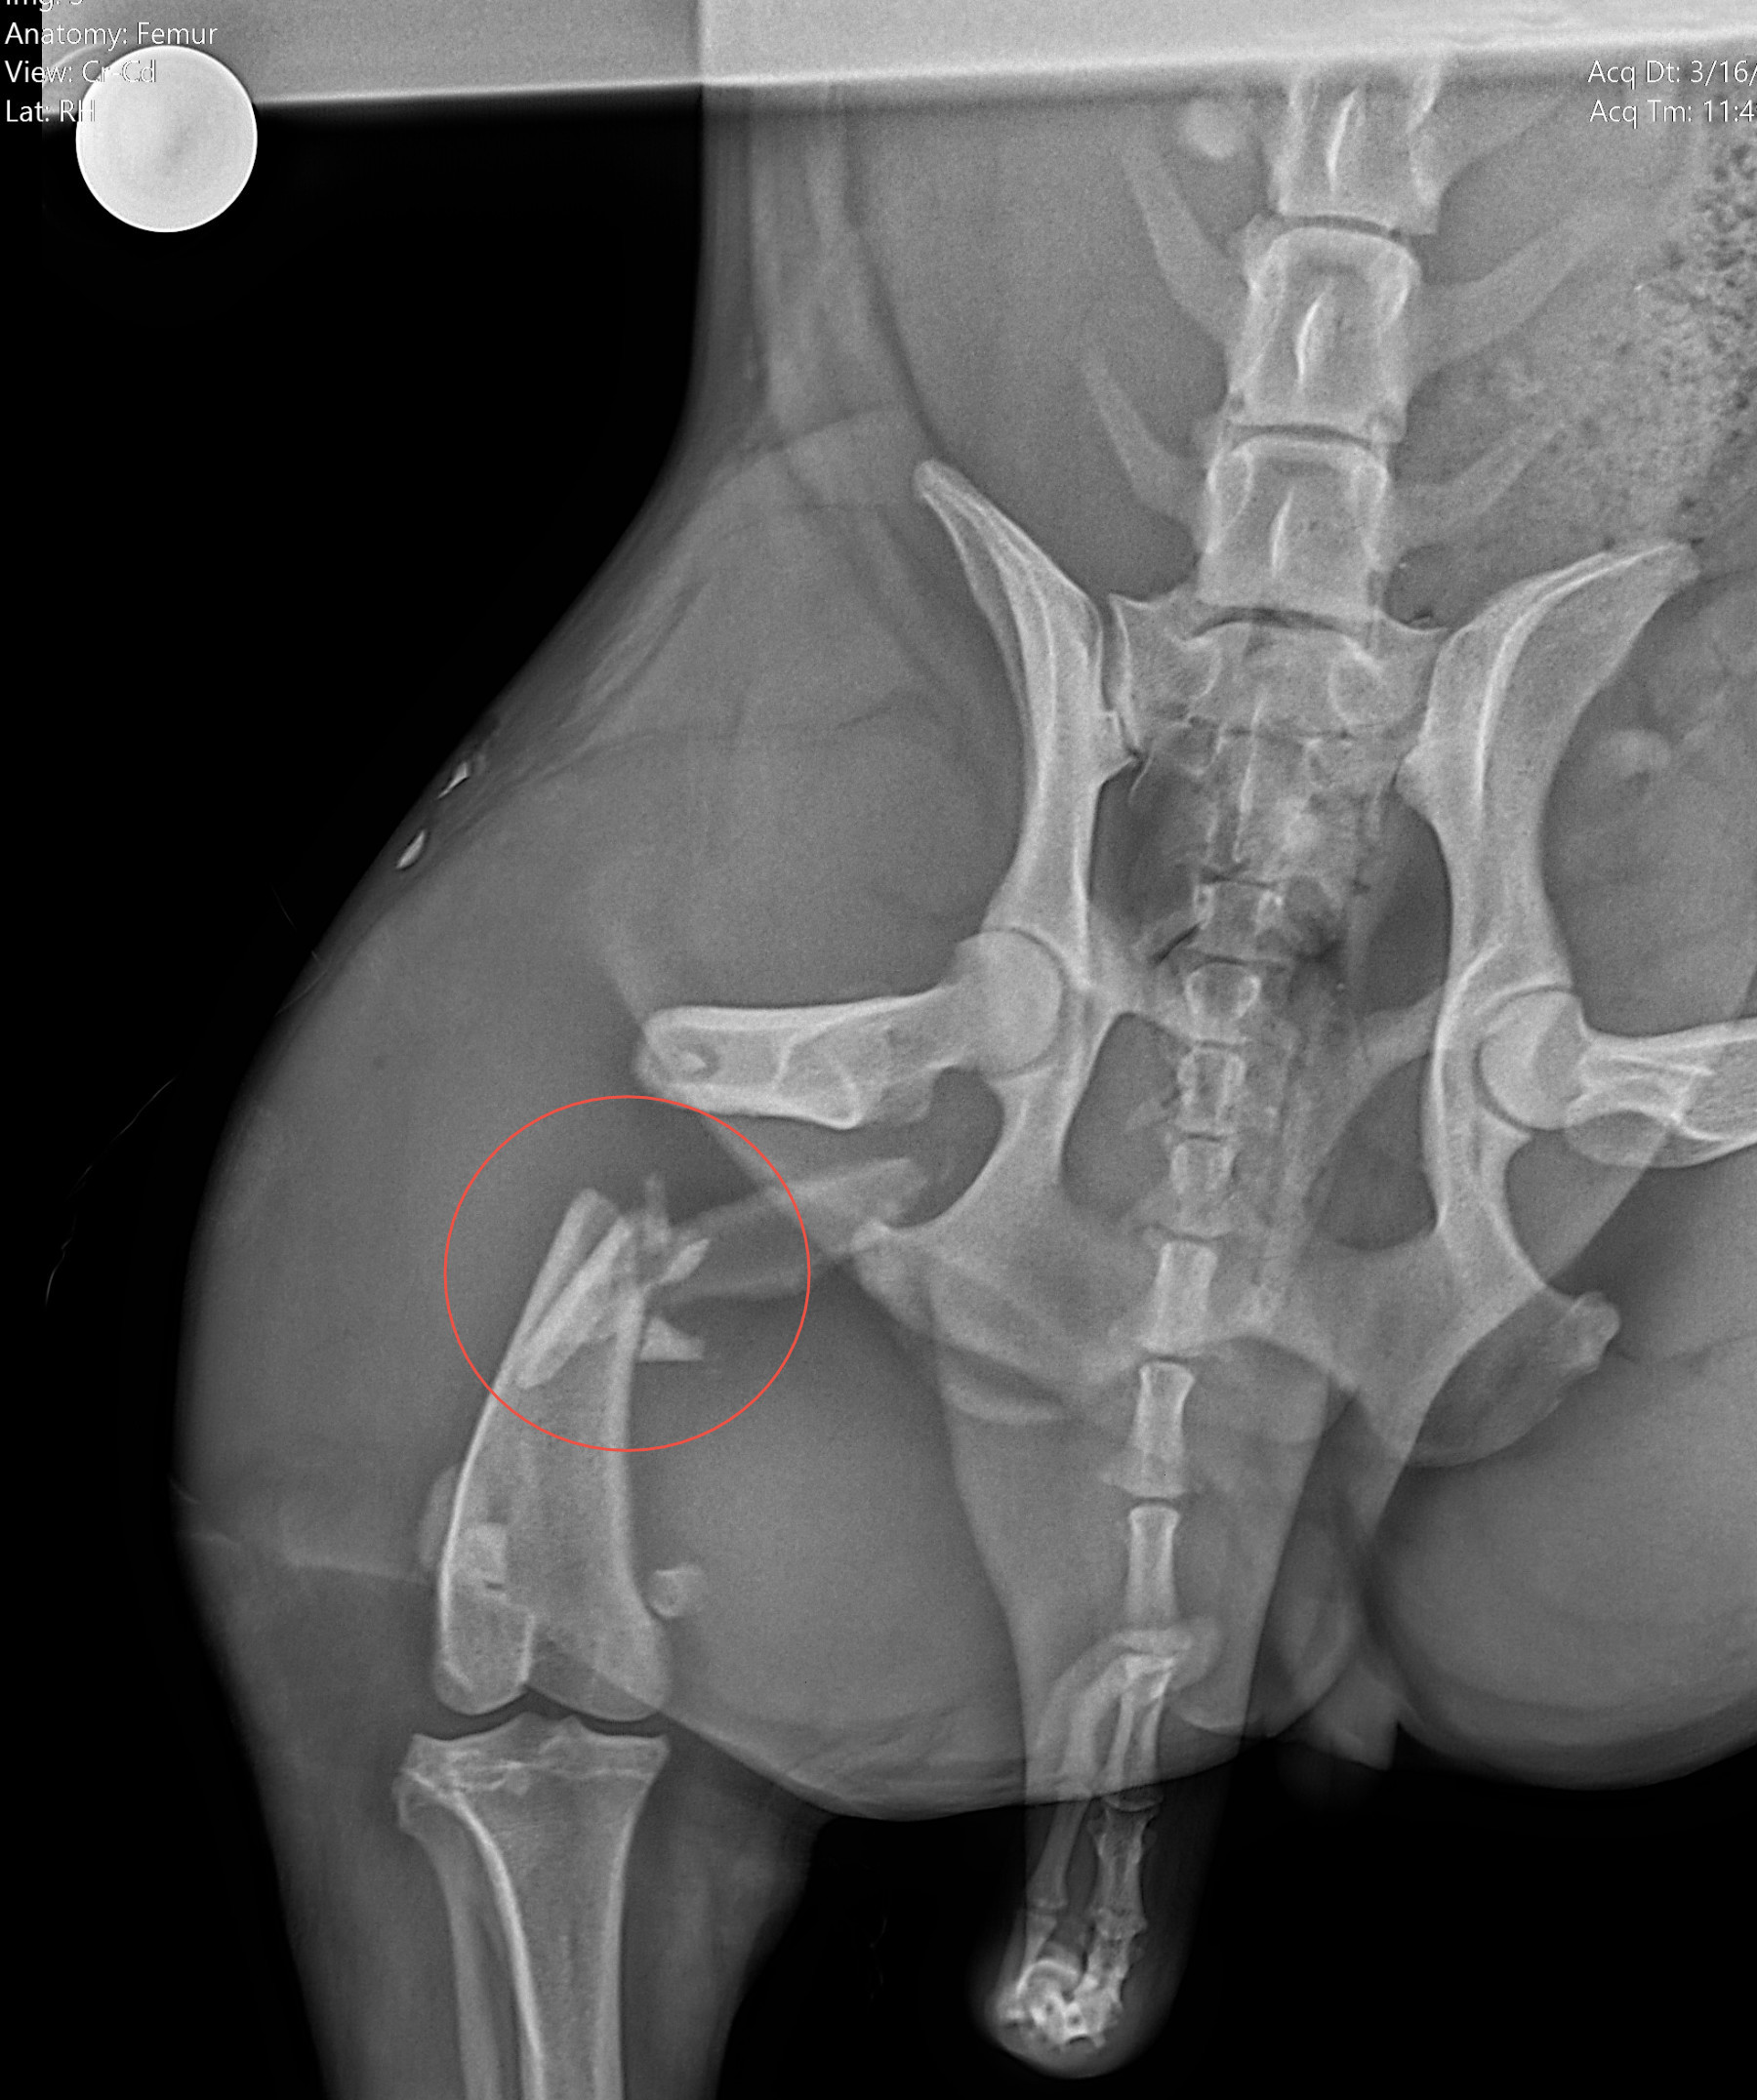

Radiología Digital como Herramienta Complementaria en el Dictamen de Bienes Muebles